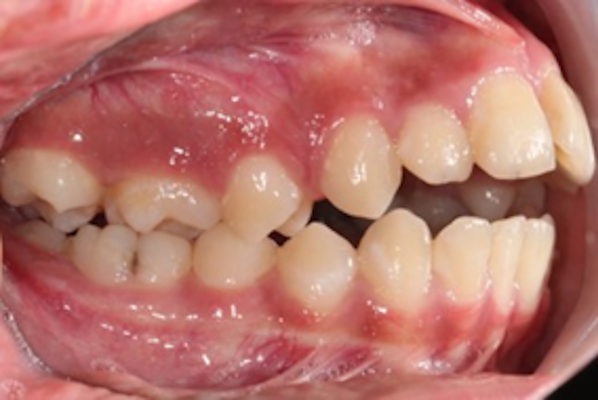

Caso de corrección de apiñamiento con ortodoncia fija

Paciente femenino de 13 años de edad, acude a consulta por dientes desalineados en la zona frontal, buscando mejorar la estética de su sonrisa y facilitar la higiene dental.

La paciente en fase inicial de tratamiento

En la evaluación clínica se observaron:

- Apiñamiento anterior superior

- Rotaciones dentales en incisivos laterales

- Desalineación en el sector estético (zona visible al sonreír)

- Relación oclusal susceptible de mejora